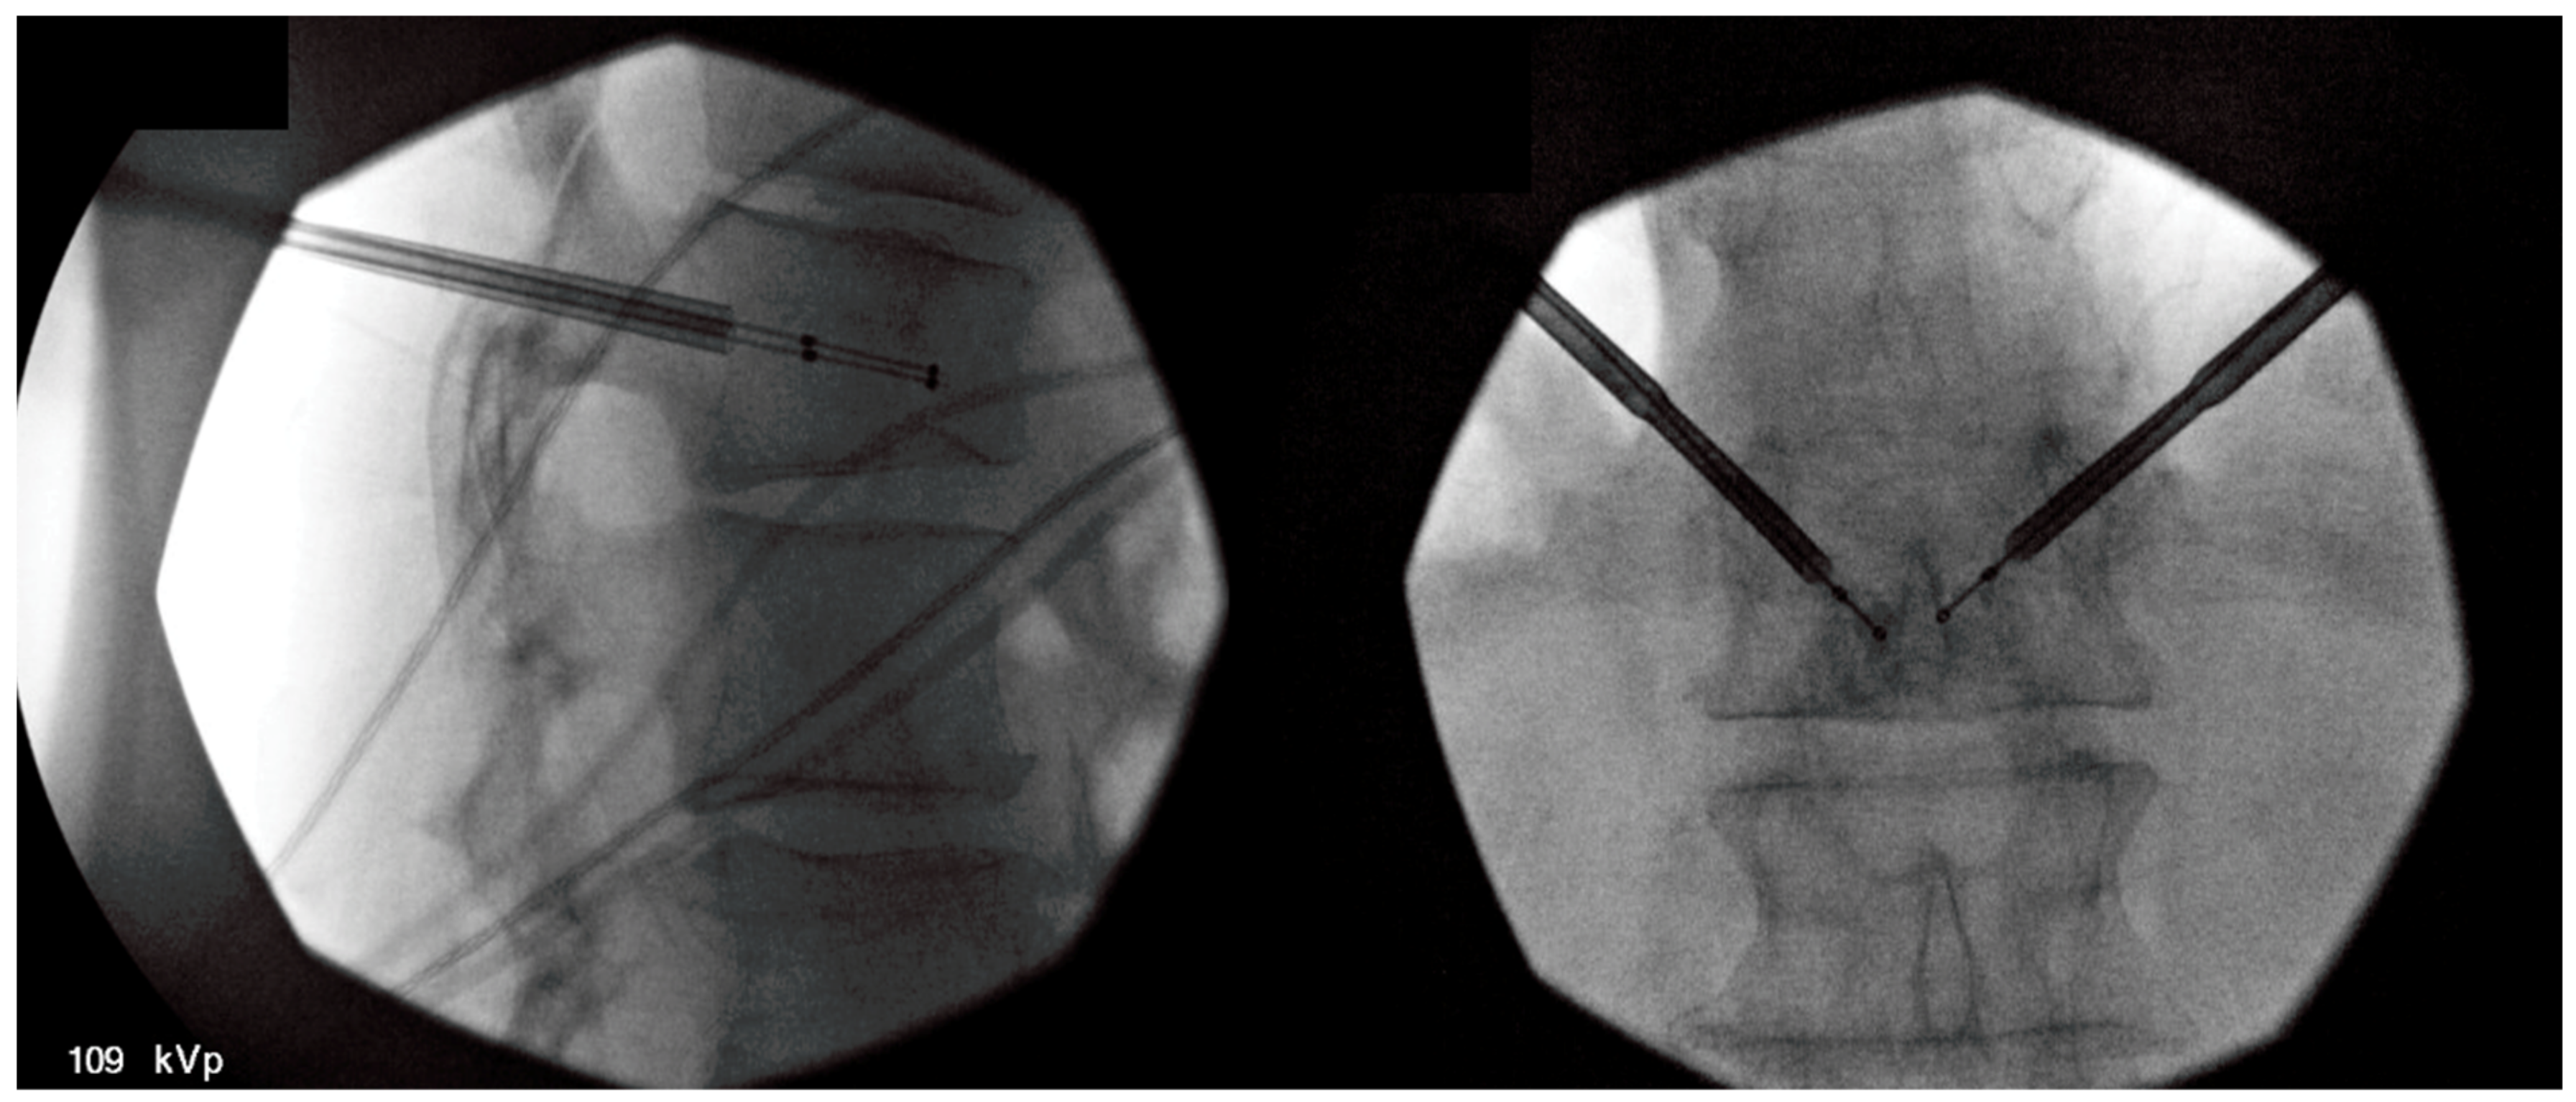

4.6. Basivertebral Nerve Ablation

- Nguyen, K.M.L.; Nguyen, D.T.D. Minimally invasive treatment for degenerative lumbar spine. Tech. Vasc. Interv. Radiol. 2020, 23, 100700. [Google Scholar] [CrossRef]

- Urits, I.; Noor, N.; Johal, A.S.; Leider, J.; Brinkman, J.; Fackler, N.; Vij, N.; An, D.; Cornett, E.M.; Kaye, A.D.; et al. Basivertebral nerve ablation for the treatment of vertebrogenic pain. Pain Ther. 2021, 10, 39–53. [Google Scholar] [CrossRef] [PubMed]

- Michalik, A.; Conger, A.; Smuck, M.; Maus, T.P.; McCormick, Z.L. Intraosseous basivertebral nerve radiofrequency ablation for the treatment of vertebral body endplate low back pain: Current evidence and future directions. Pain Med. 2021, 22, S24–S30. [Google Scholar] [CrossRef] [PubMed]

- Tieppo Francio, V.; Sherwood, D.; Twohey, E.; Barndt, B.; Pagan-Rosado, R.; Eubanks, J.; Sayed, D. Developments in minimally invasive surgical options for vertebral pain: Basivertebral nerve ablation—A narrative review. J. Pain Res. 2021, 14, 1887. [Google Scholar] [CrossRef] [PubMed]